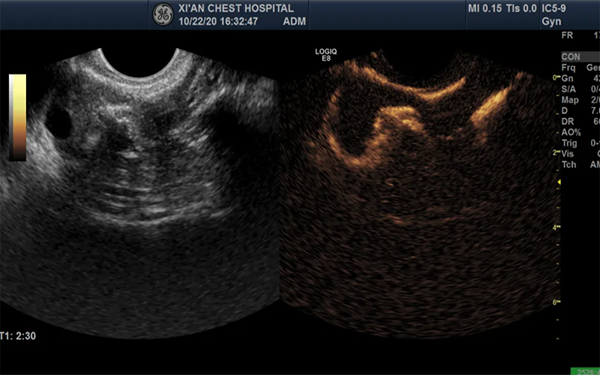

输卵管造影一般为1级疼痛,当造影剂注入到宫腔内,如果是输卵管阻塞,一般注入5ml左右,就会出现阻力感,并且患者感觉下腹胀痛。而疼痛的程度通常根据每个人的痛感有所不同,停止推注后液体又回到注射器内,表示输卵管阻塞。如果是输卵管通而不畅,注射液有阻力,再经加压又能推进,说明只有轻度的粘连,并且已经被分离,患者只有轻微的疼痛感。输卵管造影确实非常疼,并且少部分医院不麻醉也是真的,输卵管出现异常堵塞或者其他的问题是可能引起不孕的,就需要用到输卵管造影,可以让女性了解输卵管是否通畅以及宫腔各种形态,而在进行输卵管造影的时候,医生操作不熟练,患者害羞不配合医生,往往会引起疼痛。

输卵管造影由于副作用极小,并且对患者并不会造成任何的不适应感,所以输卵管造影在临床上的使用是非常广泛的,一般使用该方法进行检查的最佳时间是月经干净的3-7内,患者在手术前一定要严格按照医生的嘱咐进行准备,至于为什么说输卵管造影可怕,有以下的原因: